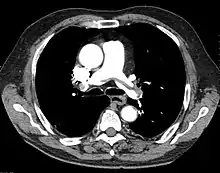

"Saddle" embolism on CT. The filling defect in the pulmonary artery is the clot.

A pulmonary embolism (PE) is an obstruction of the pulmonary arteries.[13] Deaths from PE have been estimated at ~100,000 per year in the United States. However, this may be higher in recent years.[16] Most often, the obstruction is a blood clot that traveled from elsewhere in the body. Most commonly, this is from a deep vein thrombosis (DVT) in the legs or pelvis.[13] Risk factors are conditions that increase the risk of clotting. This includes genetic (factor V Leiden) and acquired conditions (cancer).[17] Trauma, surgery, and prolonged bed-rest are common risks. Covid-19 is a recent risk factor.[18]